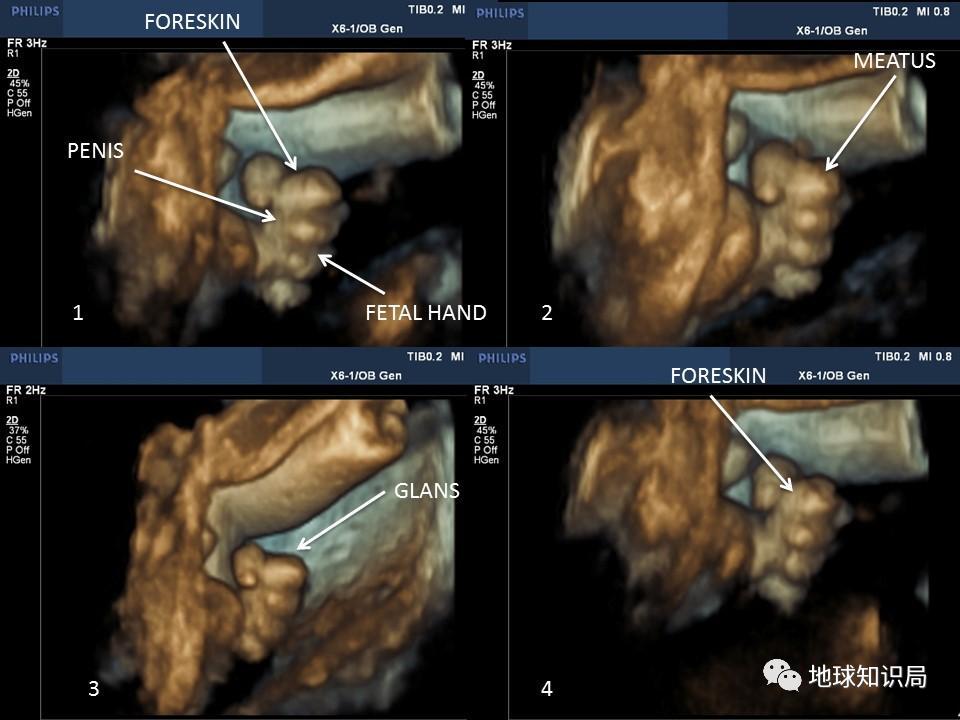

毕竟,目前观察到年龄最小有*慰自**行为的个体,是子宫内 妊娠24周的胎儿